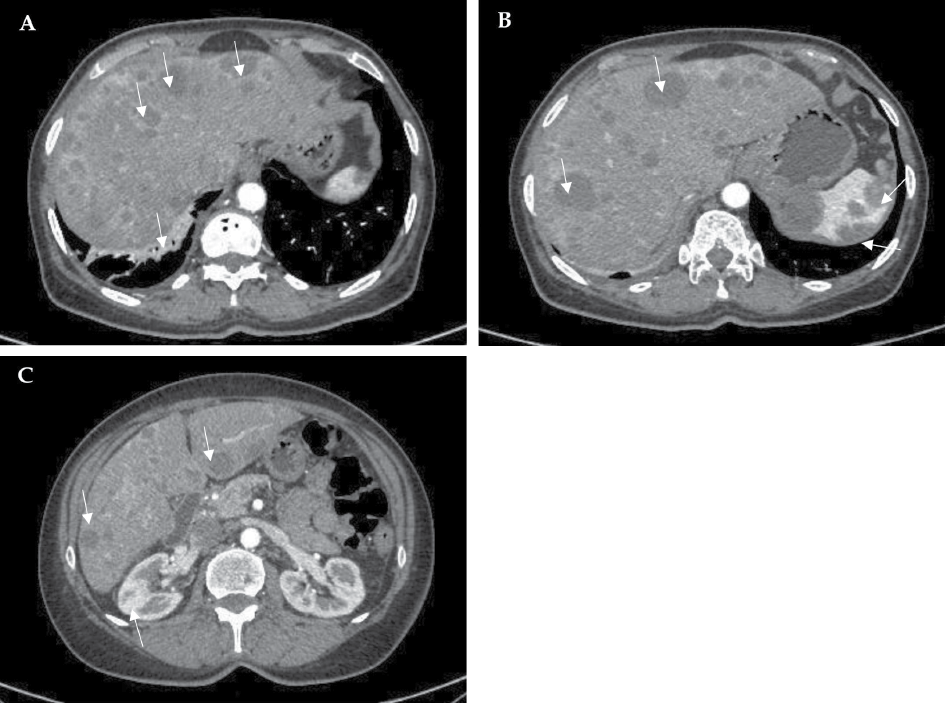

The abdominal ultrasound revealed hepatomegaly (right lobe ~171 mm) and multiple variable echogenicity liver metastases (part of which was degrading) throughout all liver segments (the biggest ~25 mm in diameter) (Figure 1, A, B). A nonhomogenous increased uterus with several calcified myomas was also observed.

Figure 1. Abdominal ultrasound images. Hepatomegaly and multiple variable echogenicity liver lesions (metastases) throughout all liver segments (the biggest ~25 mm in diameter) (A, B).